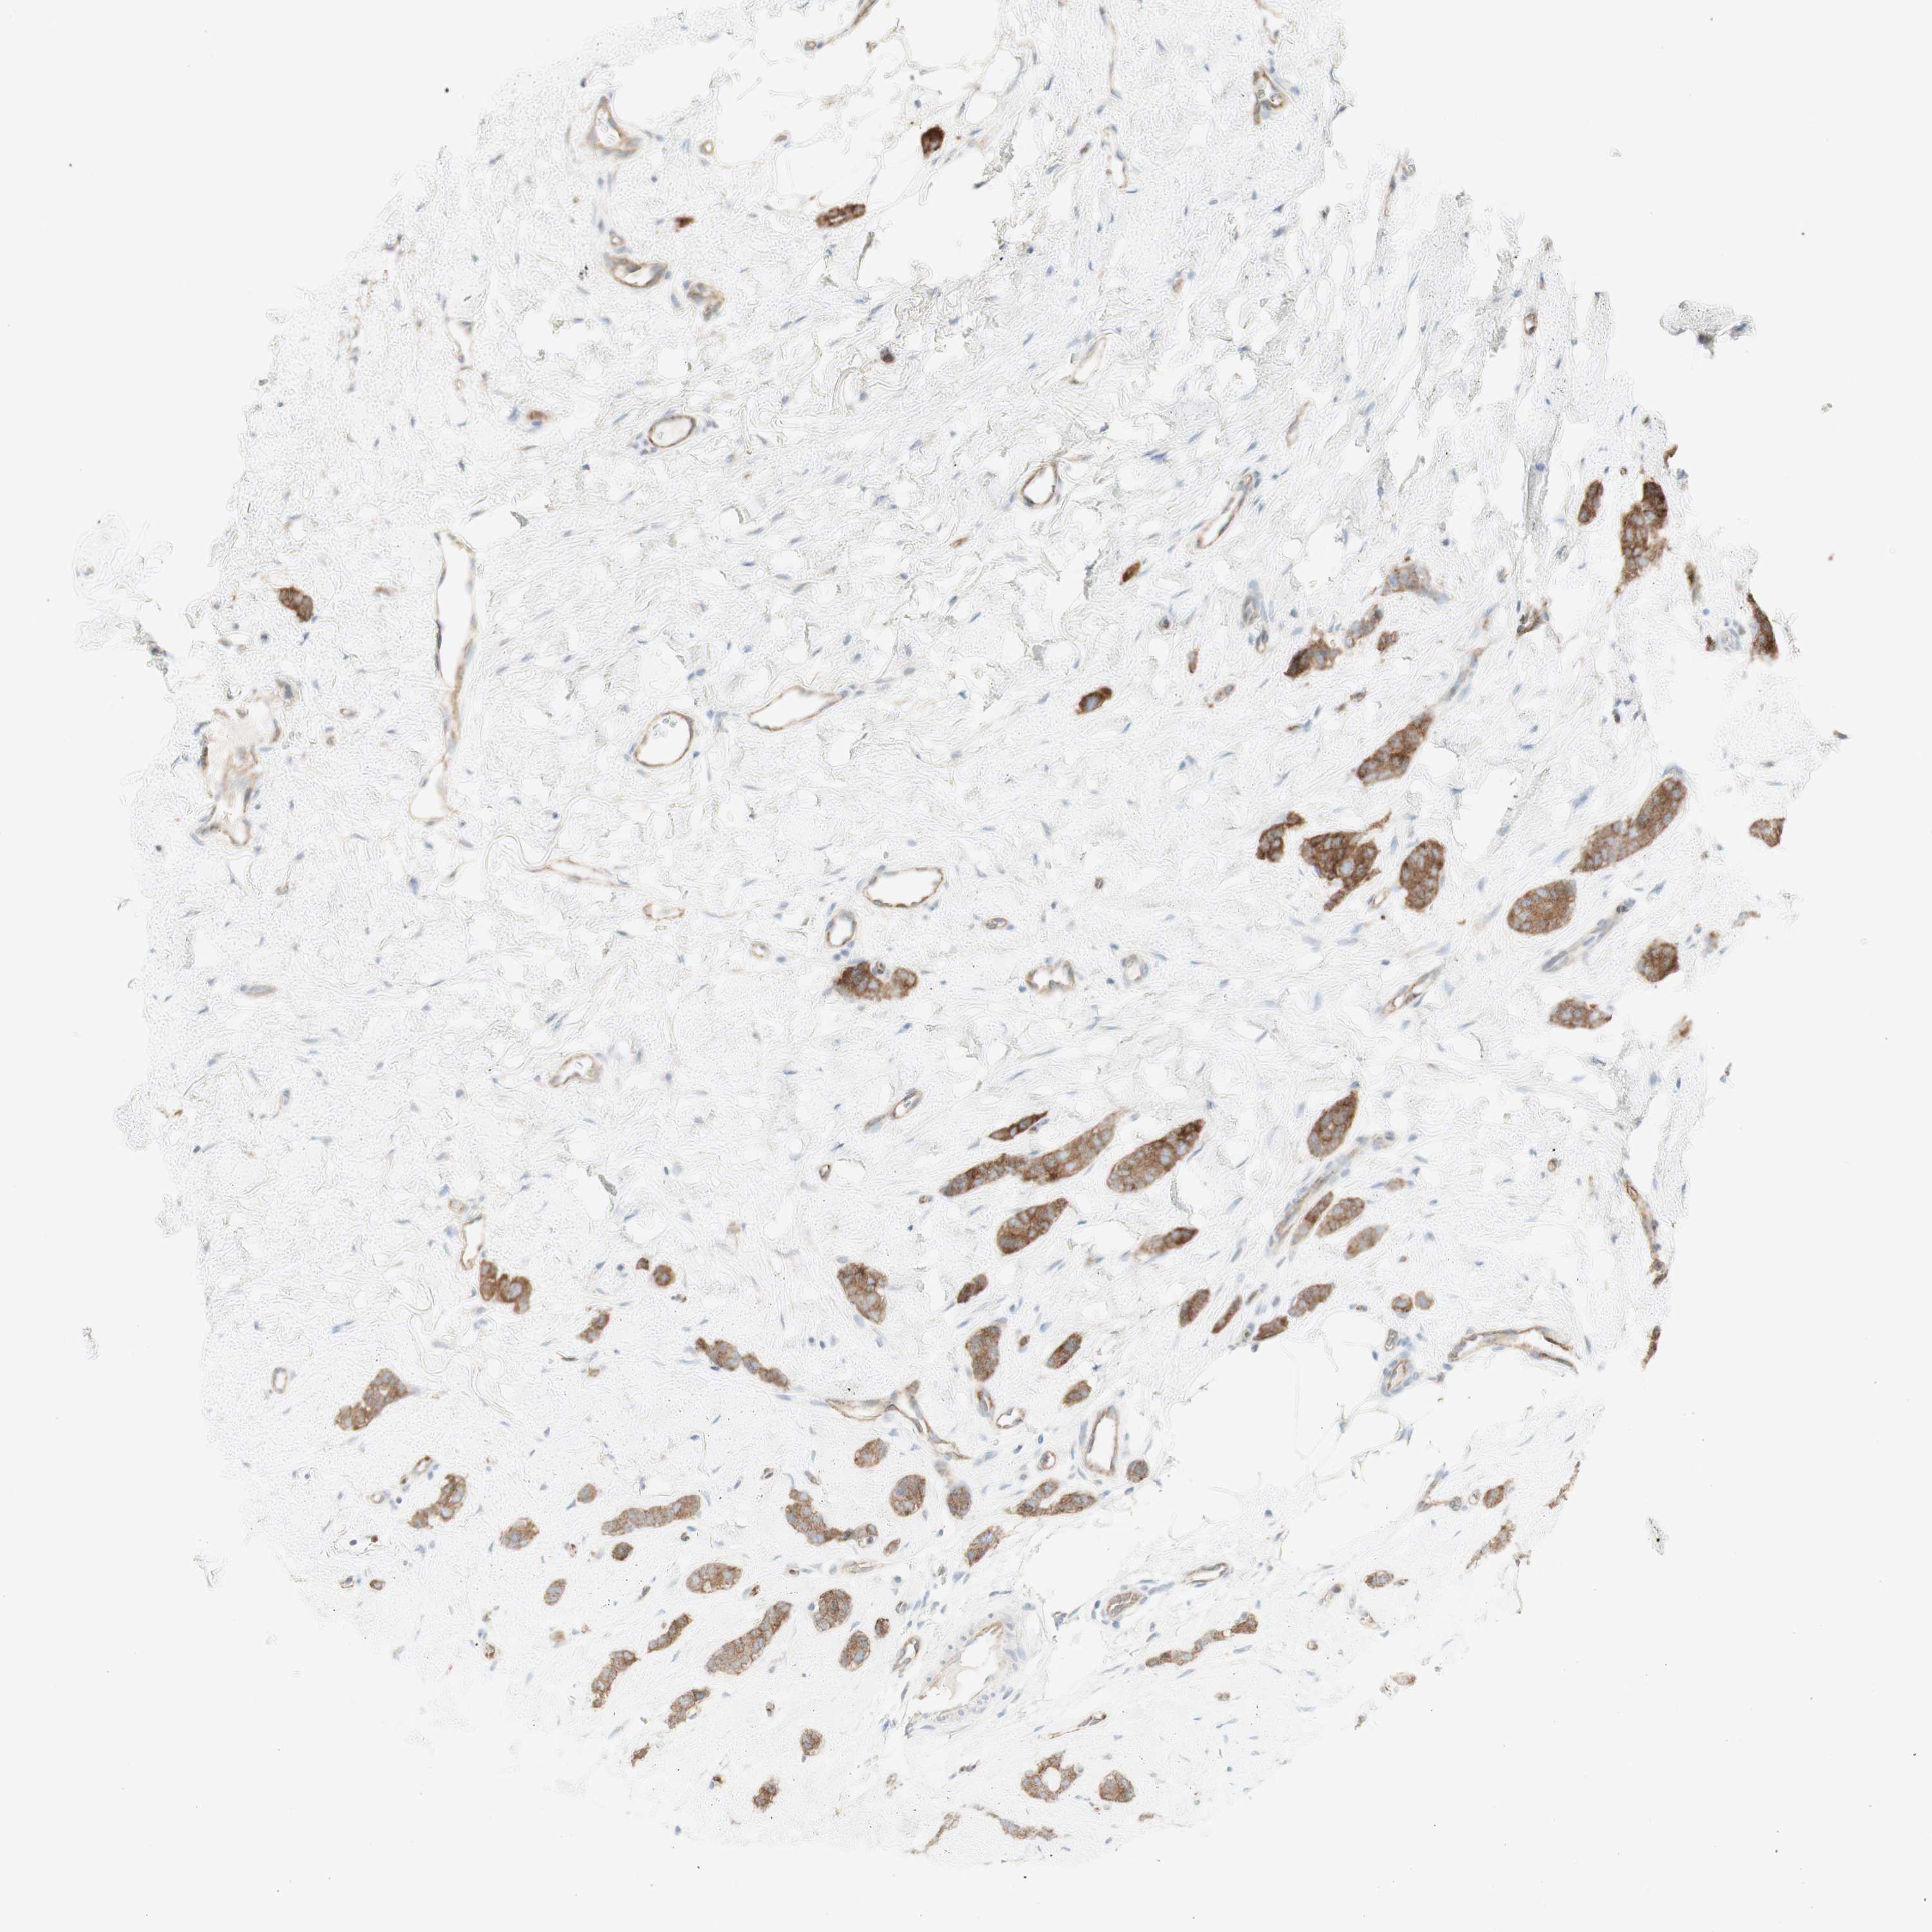

CANCER BREAST CANCER Show tissue menu

BRCA TCGA BRCA VALIDATION PROTEIN EXPRESSION